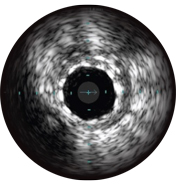

Intravascular ultrasound (IVUS) is a catheter-based imaging technology that allows physicians to visualize blood vessels from the inside out. Cross-sectional images help assess presence and extent of disease, plaque geometry and morphology, guide wire position during lesion crossing, and stent position post-treatment. The imaging transducer emits high-frequency sound waves that echo off vessel walls and are sent back to the system in varying intensities depending on the tissue. System electronics process the signal to display the cross-sectional image.

IVUS can help clarify degree and type of stenosis (i.e, MLA, plaque burden, and calcium). While IVUS can also characterize plaque rupture, thrombus, and dissection, calcium may be more common in everyday PCI. An important factor in your stenting strategy, calcium is characterized by very bright areas with acoustic shadowing that blocks out the image behind. Reverberations may also be seen.